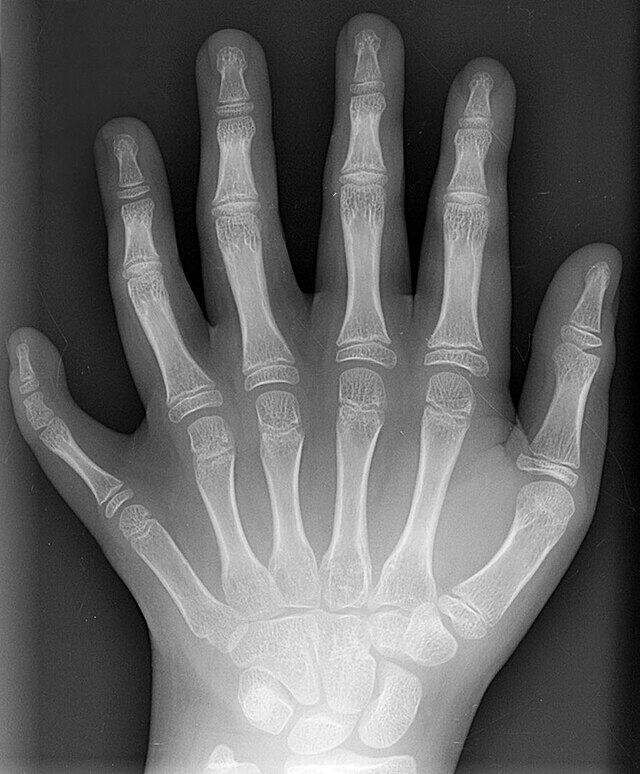

El médico puede diagnosticar la polidactilia después de conocer los antecedentes médicos de la persona y realizarle un examen físico junto con algunas radiografías, pues con ellas suele ser más fácil confirmar el diagnóstico y mostrar a los médicos si hay otros huesos afectados en las manos o los pies.

De acuerdo con el Instituto Nacional de Investigación del Genoma Humano, la polidactilia es una afección en la que una persona tiene más que la cantidad normal de dedos en las manos o los pies, es decir que se trata de una anomalía física que puede ocurrir como un defecto de nacimiento aislado.

Según Stanford Medicine Children’s Health, existen diferentes tipos de polidactilia. El primero se conoce como preaxial, que es cuando el dedo adicional está ubicado en el lado de la mano donde se encuentra el pulgar. Cuando está en el lado del dedo meñique se le denomina cubital o postaxial y si se encuentra en medio de la mano, la condición se llama polidactilia central.

Además señala que “los dedos adicionales suelen ser más pequeños que un dedo completamente formado”, detallando que su tamaño puede variar desde una protuberancia en otro dedo hasta uno con un hueso que lo conecta con el resto de la mano.